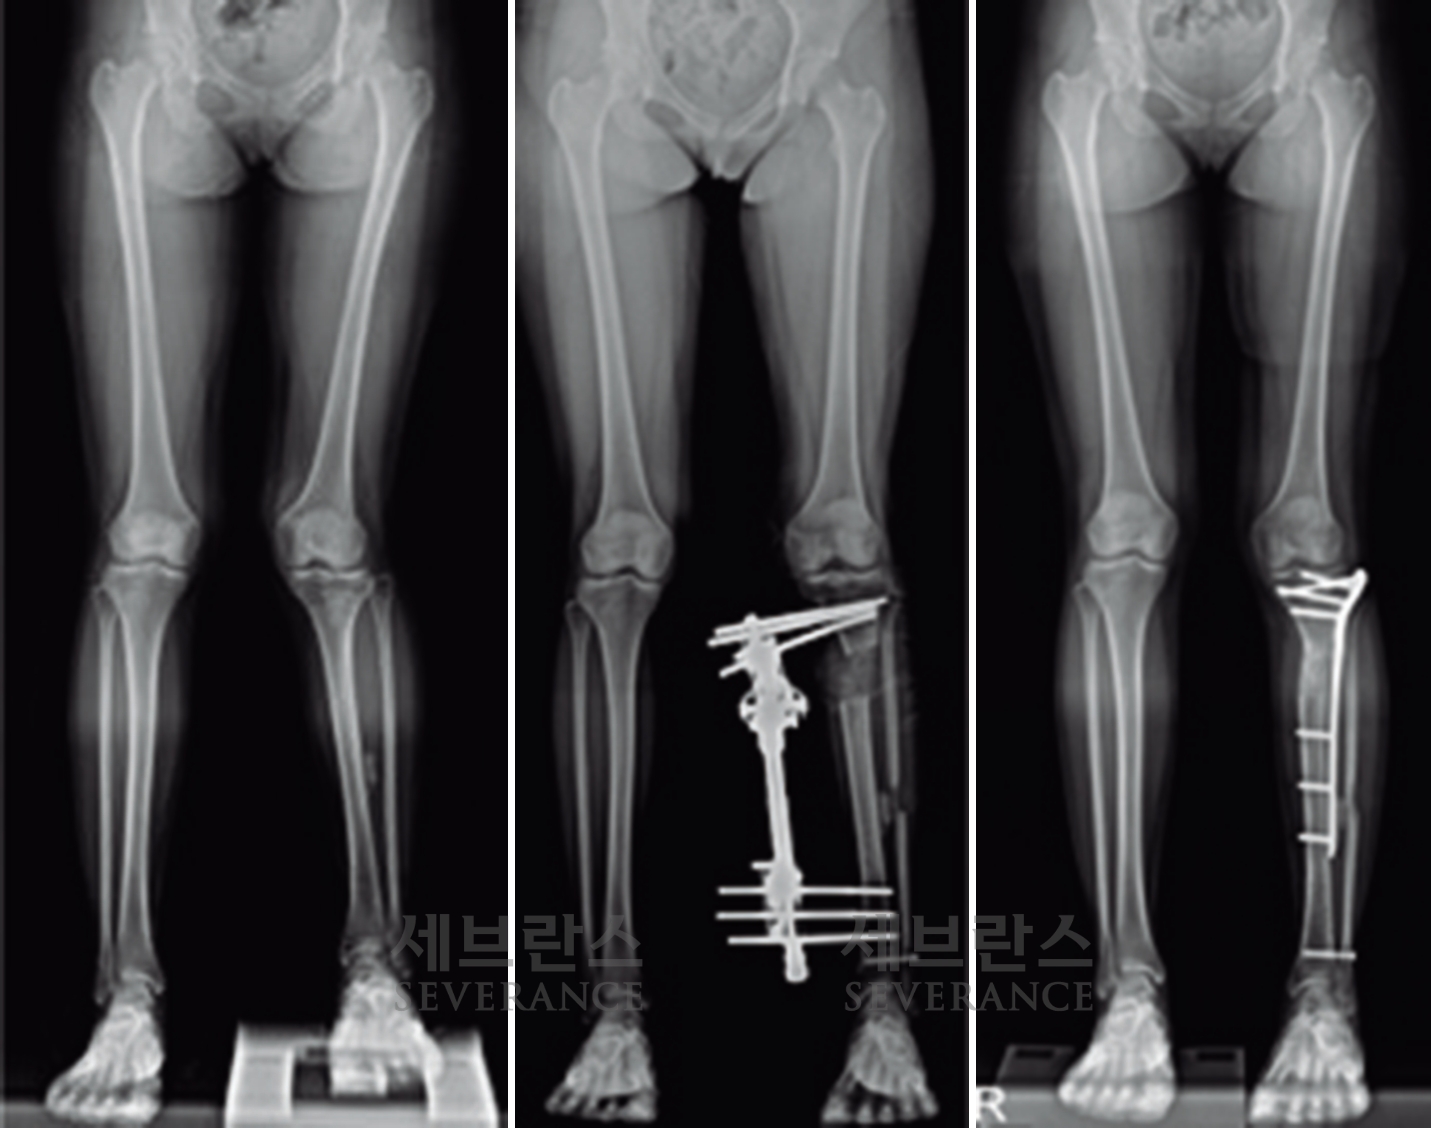

• 골연장술

양쪽 팔다리의 길이 차이가 큰 경우에 주로 시행하는 수술로, 외부 고정 장치나 내부 금속정을 이용해 뼈를 서서히 늘려 균형을 맞추는 방법입니다. 대체로 외부 고정 장치를 많이 사용하는데, 연장 기간 동안 날마다 정해진 횟수만큼 뼈를 조금씩 늘려야 하고, 핀 주변 소독도 꾸준히 해줘야 합니다. 연장된 뼈가 단단히 붙는 데도 수개월이 걸리기 때문에 환자와 보호자의 인내가 필요합니다.

구루병으로 발생한병적 내반슬(O다리) 변형에 대해

절골 교정술을 시행한 환아

성장판 손상으로 발생한 좌측 외반슬하지부동에 대해 골연장술과 교정술을 동시에 시행해 치료한 환아